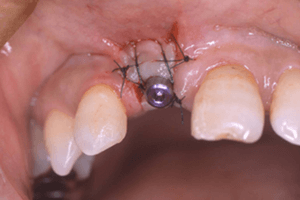

患者様自身の血液内から濃縮された止血成分を取り出して使用することで、インプラント治療や歯周治療でキズの治りを早くしたり、骨や歯周組織の再生・回復を早める再生療法です。

あごの骨にインプラントを埋め込みます。一次手術後、3~6ヶ月間の治癒期間をおくことで、インプラントと骨が強い力で結合します (オッセオインテグレーション)。この期間、仮の歯を使用できる場合もあります。歯ぐきを開いて人工の歯を取り付ける準備をします。この状態で、歯ぐきが治るまで1~6週間おきます。